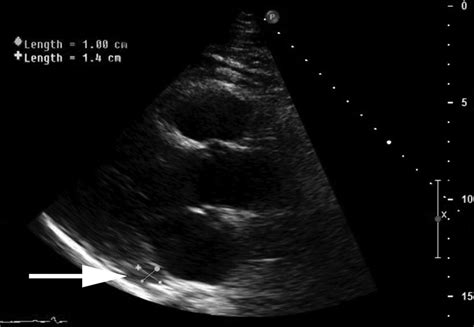

Coronary sinus (cs) • greater and smaller cardiac veins • thebesian veins • cs hellerstein study of 150 cadaver hearts cs size correlated positively with right atrial size and right atrial 55. Subcostal view showing the opening of coronary sinus into the right atrium and ostium secundum atrial septal defect (asd). Coronary sinus base and diaphragmatic surface of heart … A venous sinus opening into the heart's right atrium which drains the cardiac veins. It returns the majority of the blood supply for the left ventricle to the right atrium. Share on facebook, opens a new window. They're most numerous in the right atrium. It is present in all mammals, including humans.